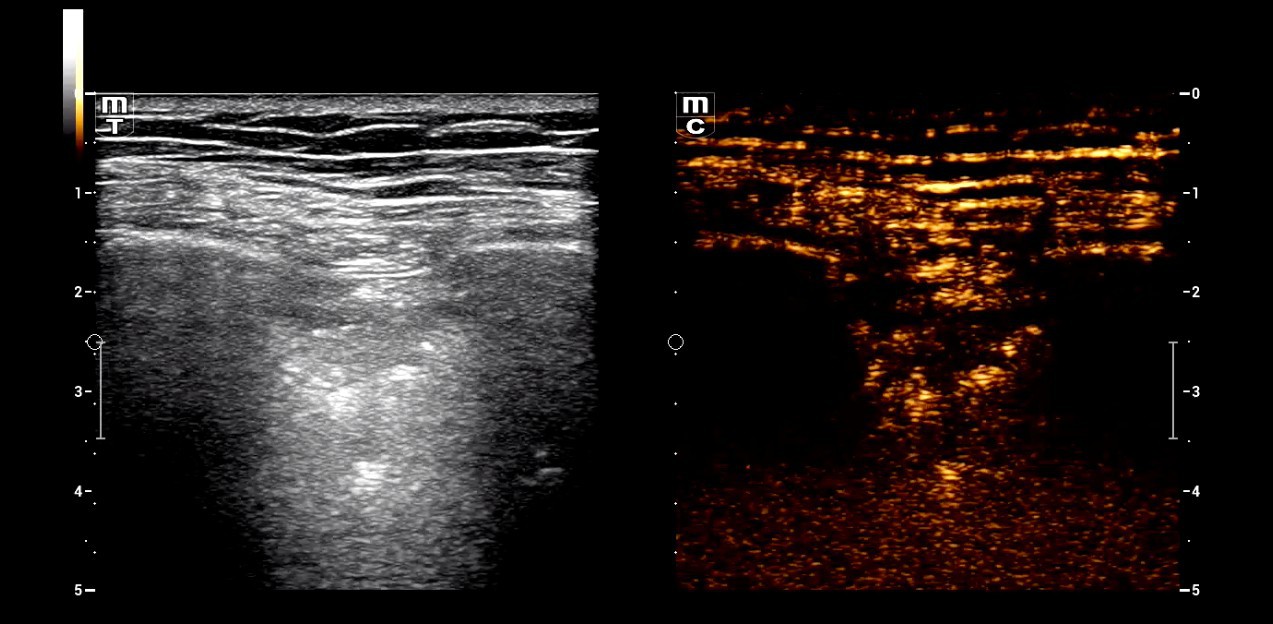

Dr. Seibel chose Resona I9 for various reasons. First, the high-end device offers excellent image quality with high resolution, as well as focused examination techniques that facilitate diagnosis. For instance, he frequently uses contrast-enhanced ultrasound (CEUS) to clarify uncertain findings.